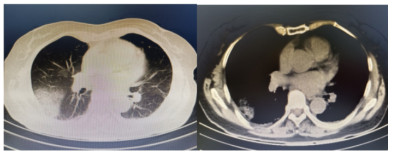

1 资料与方法患者,女,64岁,居住农村,既往有糖耐量异常5年,未正规治疗,4年前诊断为“原发性甲状腺功能亢进”,经治疗已好转。无高风险、中风险地区旅居史,无境外旅居史,无新冠病毒肺炎确诊或疑似患者接触史。2020年7月31日患者无明显诱因下在家中出现发热,体温最高39.4 ℃,伴畏寒、全身乏力,无胸闷、胸痛,无咳嗽、咳痰,无腹痛、腹泻,无黑矇、晕厥,遂在家中自服“退热药”后体温降至正常,但体温仍有反复。8月2日早晨患者再次出现发热,伴畏寒、寒战,遂至本院发热门诊就诊,予查C-反应蛋白156 mg/L,降钙素原0.64 ng/L,考虑感染性发热,遂予“哌拉西林他唑巴坦钠4.5 g每12 h一次”静滴抗感染治疗,后患者突发呼吸费力,伴咳嗽、咯血,为鲜红色血液,量较多,遂于8月2日14:18送达本院急诊抢救室。来时患者呼吸急促,有咳嗽伴咳血性痰,双侧小腿持续性钝痛,查体:血压188/86 mmHg(1 mmHg=0.133 kPa),心率168次/min,呼吸36次/min,血氧饱和度50%,体温38.6 ℃。神志清,精神软,急性面容,双侧结膜略充血,全身皮肤黏膜未见明显充血、淤血,未触及淋巴结肿大。口唇微绀,两肺呼吸音粗,可闻及明显湿性啰音,心律齐,无明显病理性杂音;腹平软,无压痛反跳痛,四肢肌力Ⅴ级,两侧病理征未引出。予心电监护、特级护理、面罩吸氧、建立静脉通道,送检血常规、生化、血气、心肌酶、凝血酶原时间系列、痰培养等常规检查,同时予送检血标本行高通量测序,完善胸部CT检查(图 1)。辅助检查结果如下:8月2日胸腹部CT示两肺感染,腹部未见明显异常。血常规:白细胞计数7.9×109/L,中性粒细胞百分比89%,血红蛋白121 g/L,血小板计数104×109/L,C-反应蛋白156.82 mg/L。血生化:丙氨酸氨基转移酶51 U/L,天门冬氨酸氨基转移酶63 U/L,白蛋白34.5 g/L,总胆红素17.4 mmol/L,肌酐74 mol/L。心肌酶谱:心肌肌钙蛋白I 0.014 ng/mL,肌红蛋白322 ng/mL,肌酸激酶同工酶3.2 ng/mL。血气分析:pH 7.435,二氧化碳分压29 mmHg,氧分压53.5 mmHg,K+ 2.6 mmol/L,Na+ 132 mmol/L,血乳酸3.1 mmol/L。新型冠状病毒抗体、核酸阴性。接诊医师初步诊断为“咯血待查:疑似肺部感染,呼吸衰竭”,治疗上予亚胺培南0.5 g静滴经验性抗感染、甲泼尼龙80 mg静滴抗炎,同时予化痰、平喘等对症、支持。17:00患者出现呼吸费力加重,10 L/min面罩吸氧下血氧饱和度仍为70%,故予紧急气管插管、机械通气,随后转入ICU,联系感染科医师会诊,结合患者病史及CT影像学表现的广泛、片状密度增高影特点,考虑钩端螺旋体病可能性大,不排除“赫氏反应”,故继续予亚胺培南0.5 g静滴每6 h一次抗感染、甲泼尼龙80 mg静滴每12 h一次抗炎、白蛋白营养支持等治疗。8月3日更改甲泼尼龙80 mg静滴每天一次。8月4日高通基因测序回报:检测出问号钩端螺旋体DNA,符合入院时推断,明确病原体后予修正诊断为肺出血型钩体病伴赫氏反应。8月5日停亚胺培南,改青霉素160万单位静滴每8 h一次。8月8日患者病情稳定,拔除气管导管,予甲泼尼龙减量为40 mg静滴1次/d,8月9日复查胸部CT提示两肺斑片状、片状密度增高影较前有所吸收(图 2),停用甲泼尼龙。8月10日转入呼吸科。8月17日复查胸部CT提示两肺斑片状、片状、条索状密度增高影,较前明显吸收(图 3)。8月20日患者好转出院。9月18日随访,复查CT提示两肺散在条索状密度增高影,基本恢复正常(图 4)。

| 图 3 8月17日胸部CT示两肺斑片状、片状、条索状密度增高影,较前明显吸收 |